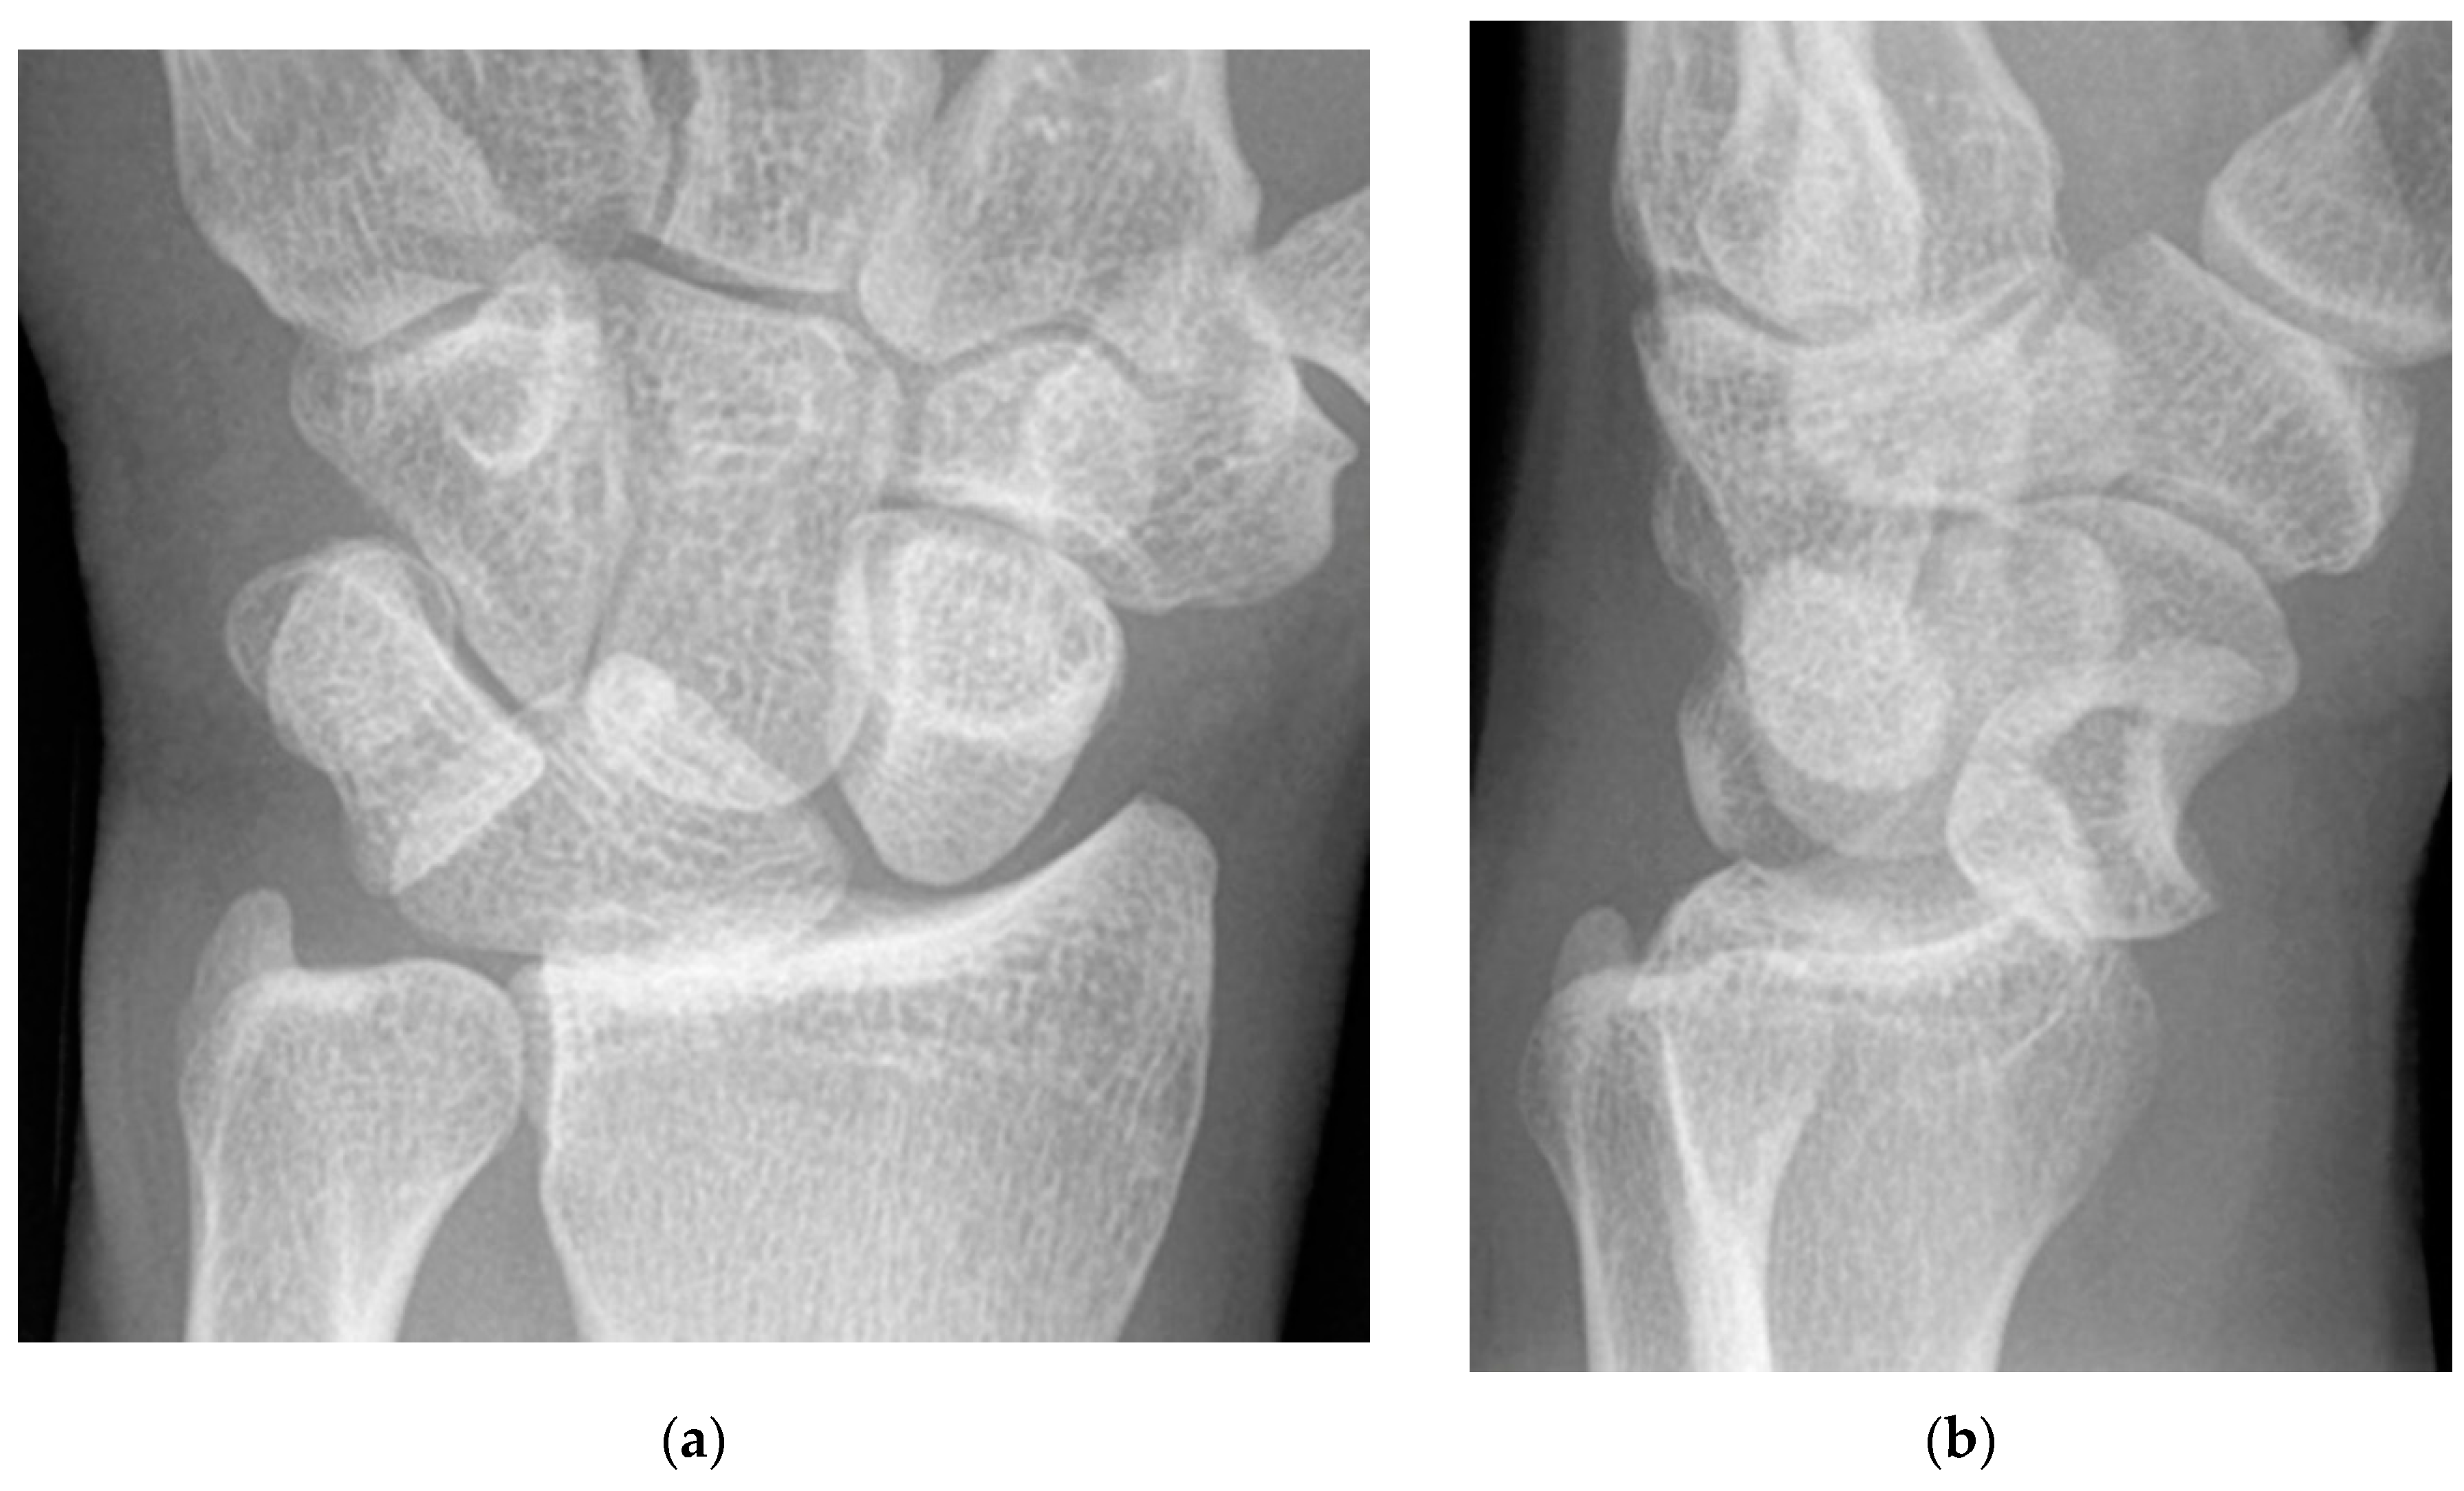

The majority of scaphoid fractures (70%) occur through the waist of the scaphoid, with 10% of scaphoid fractures involving the distal third, and 20% involving the proximal third (Figure 2 and Figure 3) [2,14]. With a scaphoid waist fracture, dorsal prominence at the fracture site due to dorsal angulation is known as humpback deformity (Figure 4). This deformity is important to recognize, as it needs to be more aggressively managed due to high risk of nonunion [15]. Additionally, if the two fragments unite with a humpback deformity, it may further destabilize the wrist. This humpback deformity may also be associated with dorsal intercalated segment instability (DISI), which will be covered in more detail later.

Figure 4. (a) Lateral radiograph of the wrist showing Humpback deformity (arrow) after a scaphoid fracture. (b) Sagittal CT reformation of the wrist showing the full extent of a humpback deformity with dorsal prominence at the site of the scaphoid fracture (arrowheads); image courtesy of Frank Gaillard, Radiopaedia.org, rID: 18269.